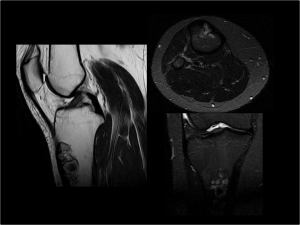

Caso número dos

Paciente de sexo femenino, de 19 años de edad, sin antecedentes de importancia. Concurre a la consulta por un dolor de comienzo insidioso en la rodilla derecha, de localización difusa. No tiene antecedentes traumáticos en el área de estudio, como tampoco quirúrgicos. Se le solicita tomografía computada sin contraste y resonancia magnética sin contraste. La imagen radiológica corresponde a la radiografía de planificación tomada con el tomógrafo, previo al estudio.